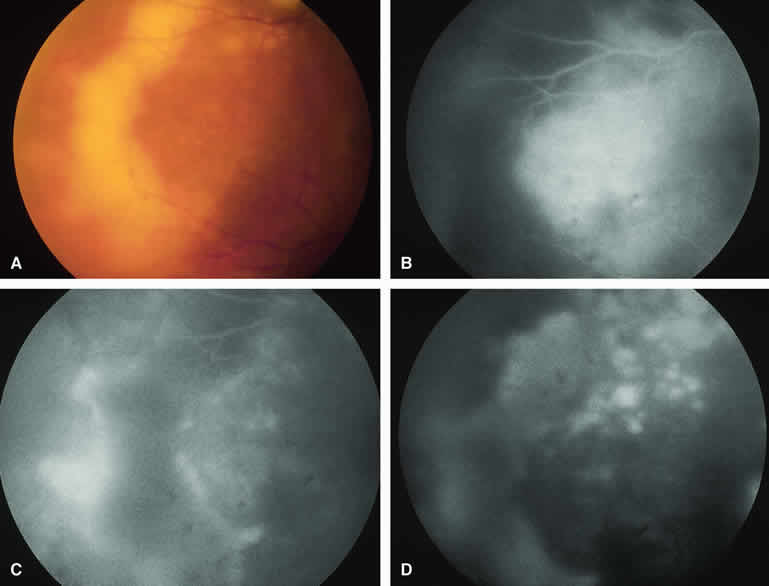

Amelanotic Choroidal Melanoma Without Invasive Features

If the choroidal melanoma being evaluated is relatively amelanotic (Figs. 11A and 12A), its large-caliber intralesional blood vessels will tend to show up more distinctly on both fluorescein angiography (see Fig. 11B, C, and D) and ICG angiography (see Fig. 12B, C, and D) than they would in a darkly melanotic choroidal melanoma. Despite its amelanotic color, the cellular component of the mass tends to be at least mildly hypofluorescent relative to the adjacent uninvolved choroid during the early frames of the study. As with melanotic melanomas, the mass usually appears at least mildly hyperfluorescent in the late-phase frames (see Figs. 11D and 12D).